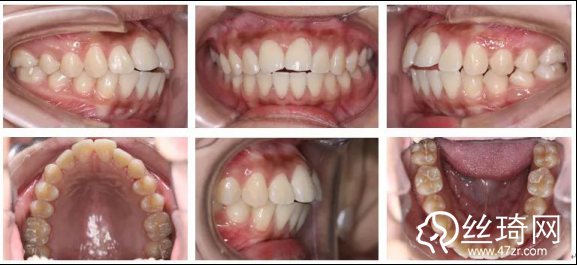

2.* 口內(nèi)檢查(以及調(diào)節(jié)前后口內(nèi)對比):

* 口內(nèi)檢查(以及調(diào)節(jié)前后口內(nèi)對比):

矯正前

口腔衛(wèi)生稍差,軟垢色素(+),牙齦略充血、腫大;恒牙列;左側(cè)磨牙遠(yuǎn)中關(guān)系,右側(cè)磨牙中性關(guān)系;前牙開牙合、深覆牙合;上下牙弓尖圓型;上下牙列輕度擁擠;上中線基本正,下中線左偏。

矯正后

上下牙列齊,前牙覆牙合覆蓋正常,中線正,雙側(cè)尖牙及磨牙關(guān)系中性,雙側(cè)后牙尖窩關(guān)系良好。